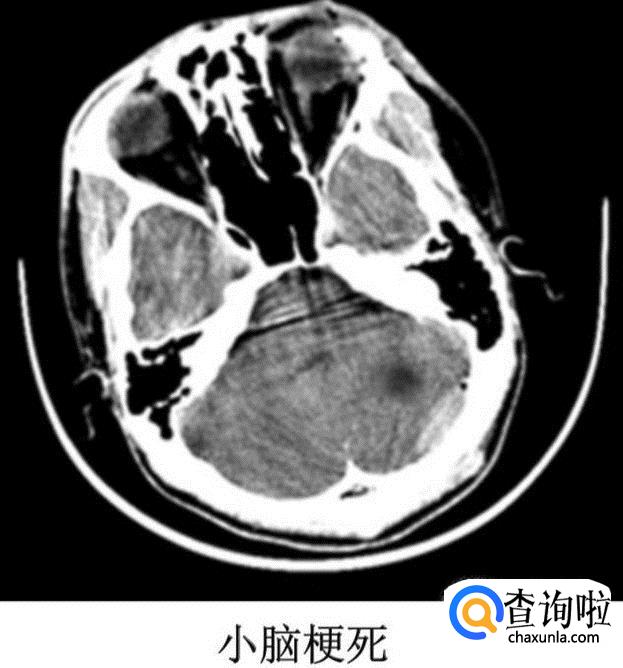

脑梗死

按解剖部位可分为:

① 大脑梗死:大梗死---超过一个脑叶,5cm以上;中梗死---小于一个脑叶 3-5cm;小梗死1.6-3cm;腔隙性梗死---1.5cm以下;多发性梗死---多个中小及腔隙性梗死。

② 小脑梗死

③ 脑干梗死